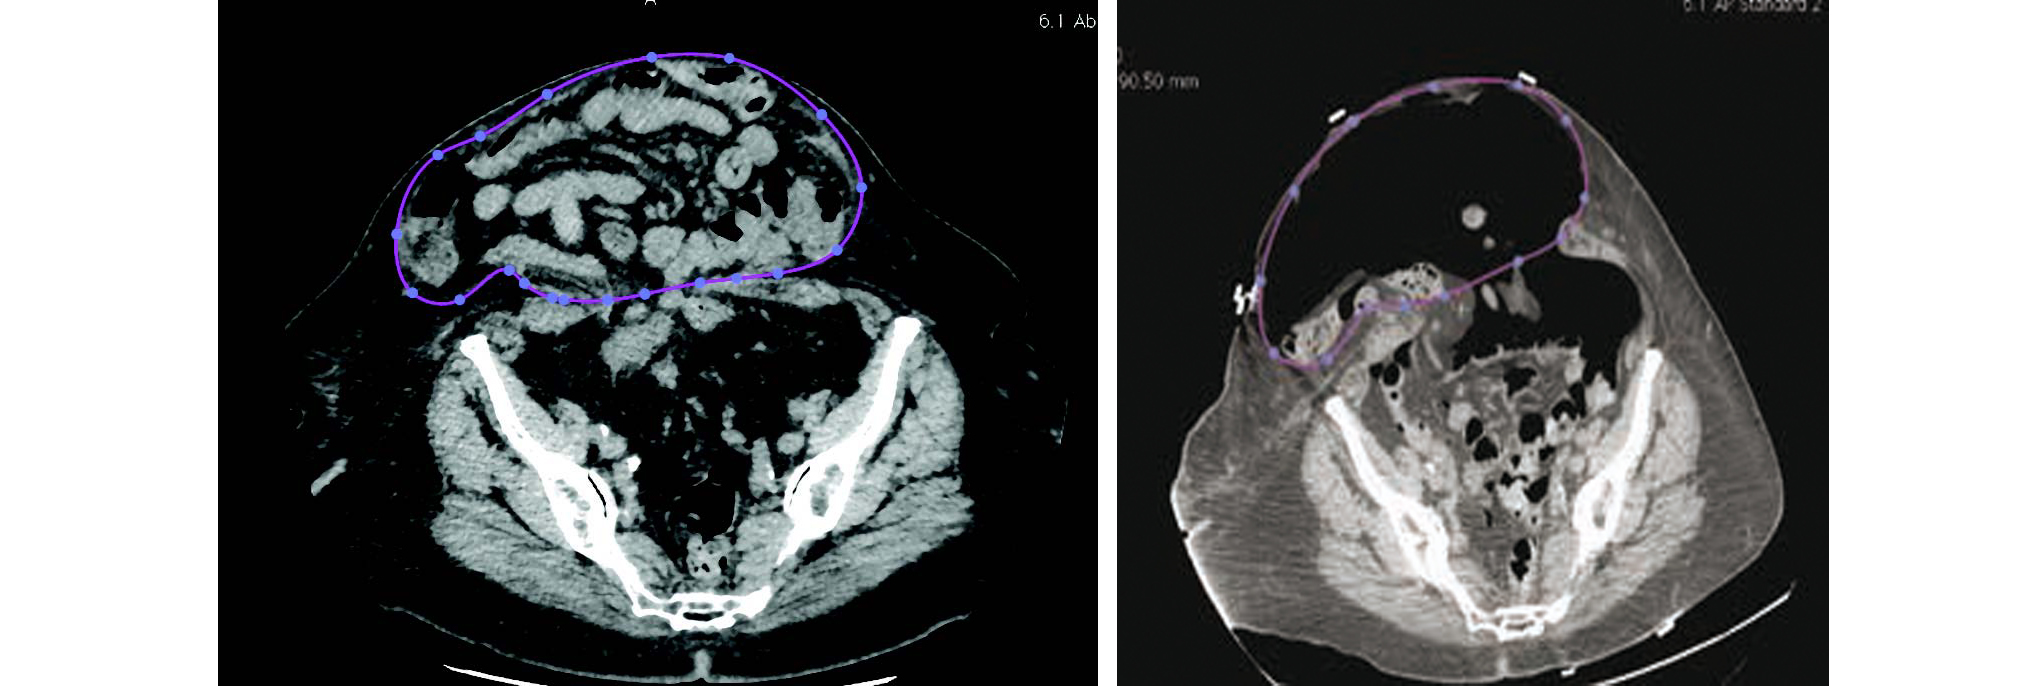

Une fois l'objectif de pneumopéritoine atteint, un bilan pré-opératoire est réalisé, comprenant de nouvelles EFR ainsi qu'un nouveau scanner abdomino-pelvien, permettant de calculer de nouveau la volumétrie.

Figure 6 Nouvelle mesure de volumétrie avant de réaliser le geste chirurgical.

Par ailleurs, la préparation pré-opératoire est essentielle afin de limiter les complications chez ces malades souvent fragiles et comorbides. La prise en charge doit être pluridisciplinaire, notamment respiratoire et cardiovasculaire. L'insufflation d'un pneumopéritoine pré-opératoire doit être vu comme un test thérapeutique à l'augmentation de la pression intra-abdominale, et il ne faut pas hésiter à faire demi-tour en cas de mauvaise tolérance clinique. Enfin, la réévaluation scanographique avec mesures des nouveaux volumes péritonéaux, nous parait essentielle, afin de réévaluer la réductibilité ou non de l'éventration avant d'effectuer le geste chirurgical.